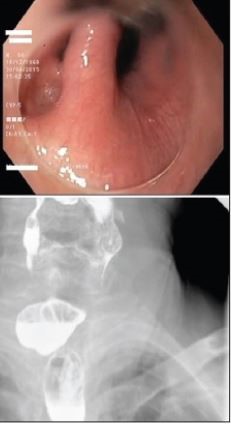

Attachments - Εκκόλπωμα Zenker

Εκκόλπωμα Zenker